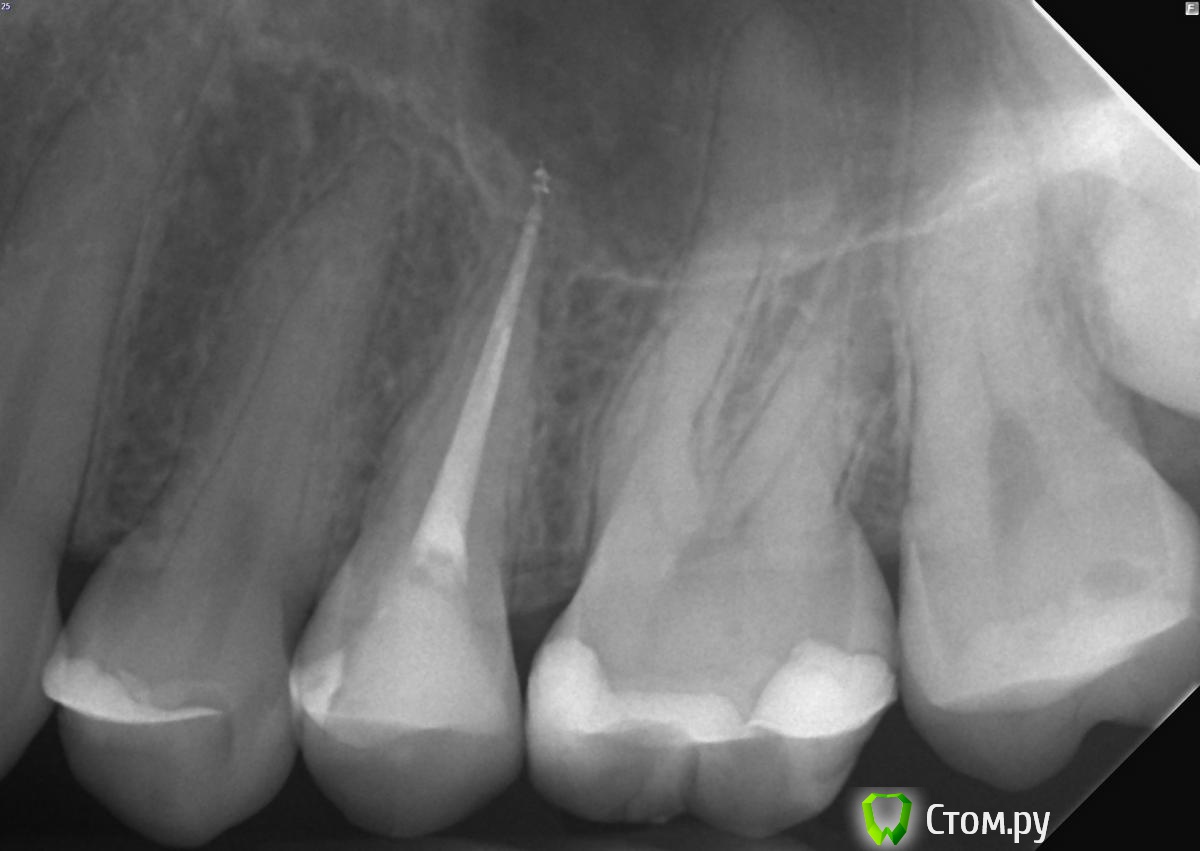

felicidade Опубликовано 25 сентября, 2014 Поделиться Опубликовано 25 сентября, 2014 Добрый день! Хотелось бы спросить мнение докторов относительно зубов 24 и 26: 1) судя по рентген-снимкам, у меня в 24 зубе кариес под пломбой. Скажите, пожалуйста, насколько он кажется близким к нерву? Может, я зря записалась к обычному терапевту, и мне надо сразу топать к эндодонту?2) зуб 26: виден ли там вторичный кариес? Я меняла пломбу в апреле этого года и заплатила то ли 5, то ли 6 тысяч за этот зуб, под прежней пломбой уже был кариес. Было бы очень обидно узнать, что новую пломбу надо снова менять Спасибо заранее и хорошего дня Ссылка на комментарий

Korel Опубликовано 25 сентября, 2014 Поделиться Опубликовано 25 сентября, 2014 По снимкам страшного ничего не вижу, приветствую Вашу запись на осмотр к терапевту, он Вам очно , думаю, ответит точнее. Ссылка на комментарий

Паращук Роман Опубликовано 25 сентября, 2014 Поделиться Опубликовано 25 сентября, 2014 То что вы можете считать кариесом,может быть не рентгенконтрастным м-ом жидкой формы. Ссылка на комментарий